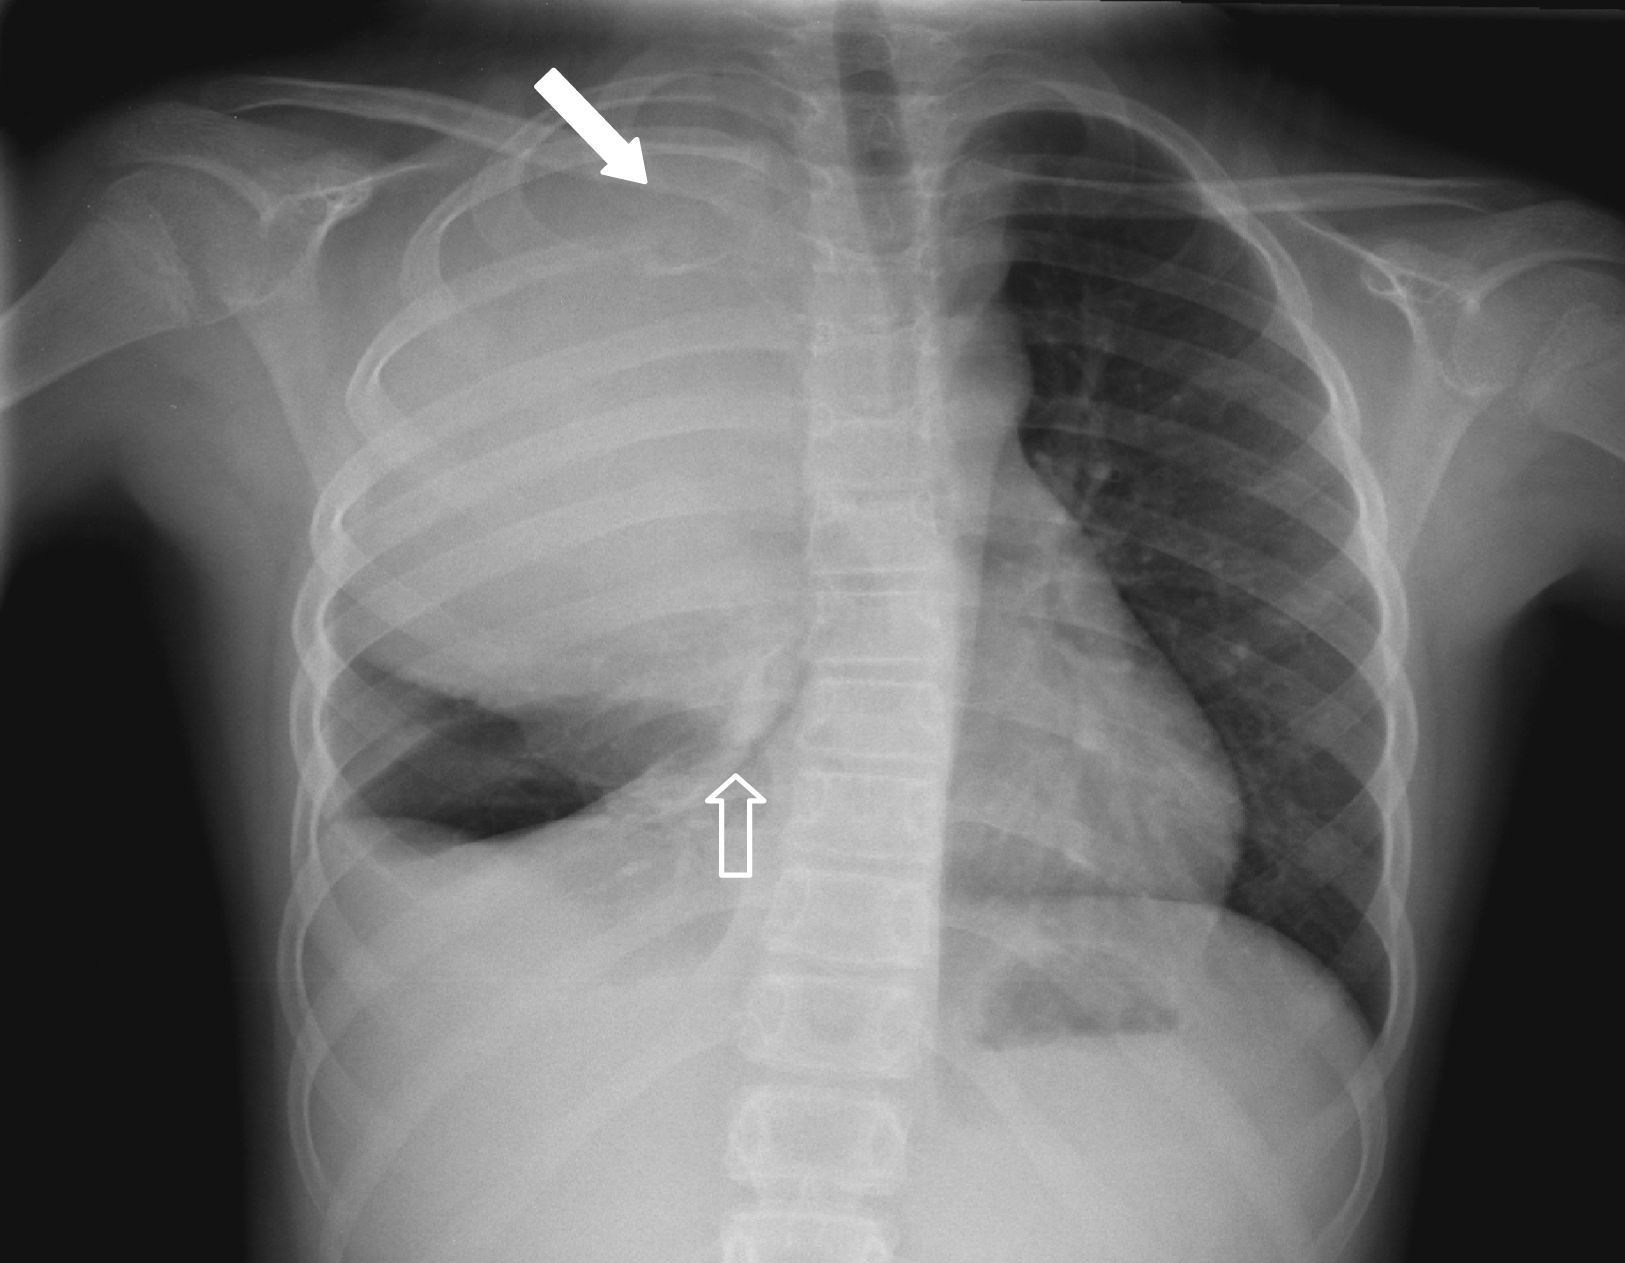

Radiología Solución del caso 9. Tumor de Askin

Solución del caso 9. Tumor de Askin

Solution to case 9. Askin tumor